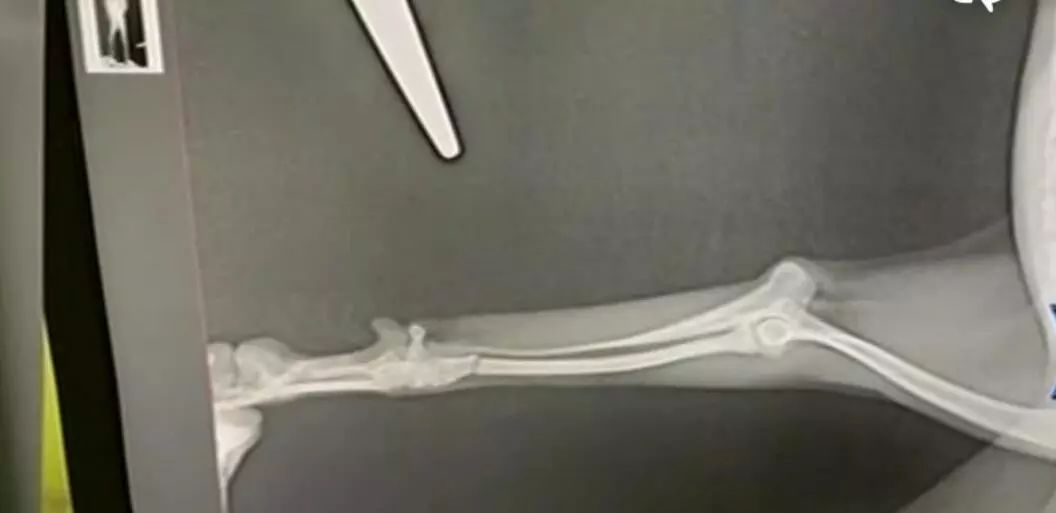

在杭州瑞派虹泰宠物医院环城总院,我们见到了刘女士的宠物狗米奇。一个多月的时间里连续两次骨折,小狗看上去很可怜。刘女士说米奇的第一次骨折是在一个多月前,因为没有监控,骨折原因不明确。

当时,在记者的协调下,双方签订调解协议,医院负责治疗米奇骨折,直至痊愈,并补偿刘女士5000元。但没想到,过了一个多月,在虹泰宠物医院相城分院的米奇又骨折了。我们注意到事发现场有一个*控器监**,但医院表示这个监控无法回放。所以狗狗如何骨折,现在还是不清楚,刘女士提出要求赔偿买狗的35000元。